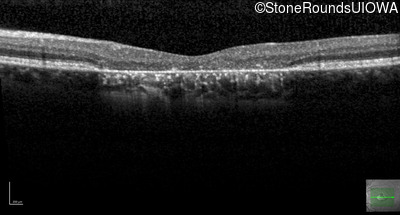

This 22 year old man had macular abnormalities noted incidentally at a routine eye exam at age 19. Since then, he has experienced a gradual loss of acuity particularly in the left eye.

| AR Stargardt Disease | ABCA4 | Tyr245Stop TAT>TAG | Unknown | AR |